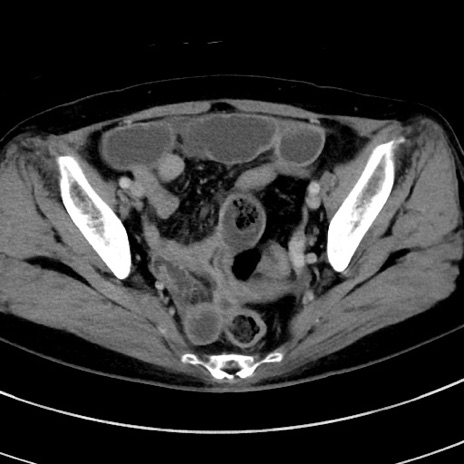

症例9(横断像)

【症例】 60歳代女性

【主訴】むかつき、みぞおちの痛み

【現病歴】3日前よりむかつきがあり、食事がとれない。

【既往歴】糖尿病

【身体所見】発熱なし、心窩部圧痛軽度あるも、腹膜刺激症状なし。

【データ】WBC 7400、CRP 1.92